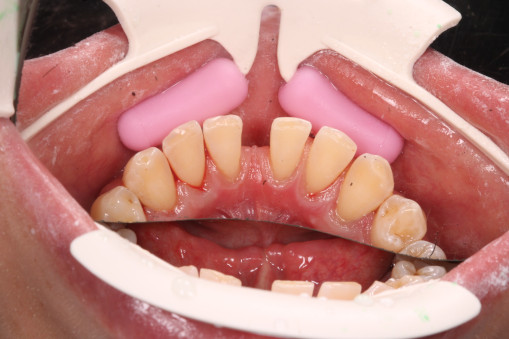

А прежде, чем вы посмотрите фотографии «до» и «после» лечения слизистой оболочки полости рта, проведенных в нашей клинике, хочу поблагодарить большое количество наших пациентов, которые поверили, прониклись нашей концепцией, и мы вместе, именно вместе победили болезни десны, гингивит и пародонтит!

До/после лечения